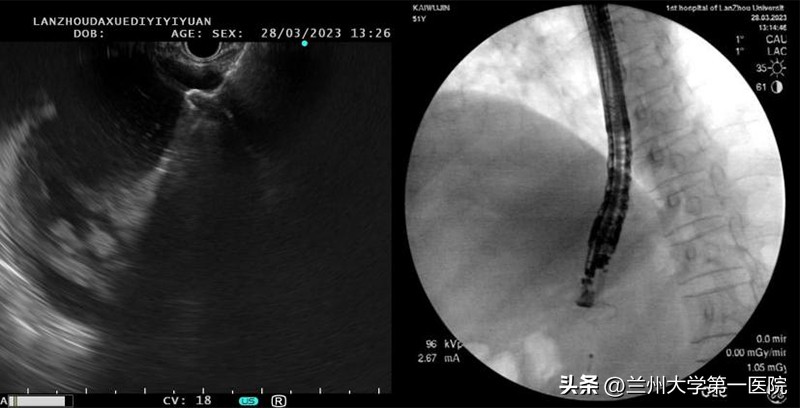

患者因胰周巨大囊性肿物从陇南转入兰大一院普外科进行治疗。入院后,普外科通过超声内镜检查进一步明确了诊断,该患者为胰腺假性囊肿合并囊腔感染。随后,普外科组织开展病例讨论,在普外科主任张磊的指导下,手术团队通过超声内镜检查引导下开展了胰腺假性囊肿穿刺置管引流术,并且在未使用X线辅助的情况下,手术仅用时5分钟便成功放置Axios支架,术后患者腹痛症状消失,手术效果明显。

近年来,随着超声内镜技术日趋成熟,超声内镜可以准确判定囊壁与胃壁之间的距离,清晰观察到其间是否存在较大血管,从而确定最佳穿刺点,并清楚显示穿刺及置管的全过程,保证手术安全可控。超声内镜引导下电切引流支架置入术可根据内镜超声检查成像引导,从胃肠道进入,利用电刀切开胰腺囊肿,并通过支架建立胃与囊肿的引流通道,进行引流胰腺积液,同时还可进行胰腺坏死组织清创术,手术过程快速高效,支架移位风险极低,更有利于患者康复。